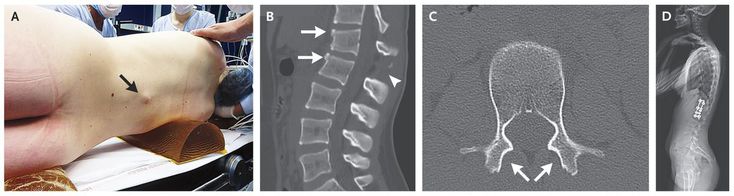

A 14-year-old girl presented to the emergency department after a car accident; she had been wearing a lap–shoulder seat belt. She had severe back pain but had normal strength and sensation of touch in her legs; she reported no paresthesias. Palpation of the lumbar spine revealed prominence of the spinous process of the first lumbar vertebra (Panel A, arrow) and an increased gap between the first and second lumbar spinous processes, findings that aroused suspicion of a flexion–distraction injury. Computed tomography revealed disruption of the ligaments in the posterior column (Panel B, arrowhead) and the middle column, as well as disruption of the L1–L2 intervertebral disk in the anterior column. There were also fractures of the anterosuperior aspects of L1 and L2 (Panel B, arrows) and dislocation of the L1–L2 facet joints (Panel C, arrows; the inferior articulating facets of L1 are absent). These fractures are characterized by violent flexion, with all elements posterior to the axis of rotation submitted to distraction forces; the fractures are unstable and require surgical treatment. The patient underwent T12–L2 fusion (Panel D) and was pain-free 4 months after surgery. She was authorized to return to swimming 4 months after surgery and to all sports activities 2 months later.